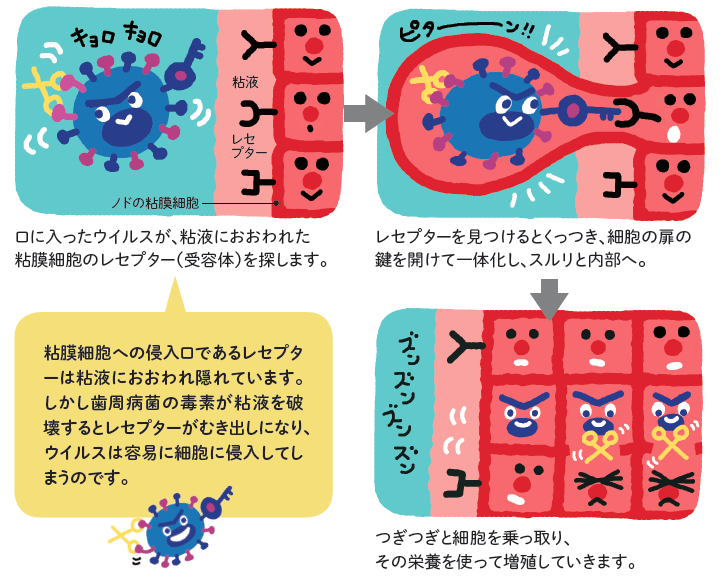

ウィルス感染は歯周病菌により口腔粘膜の細胞が破壊され、レセプターがむき出しになった細胞にウィルスが付着することで感染します。